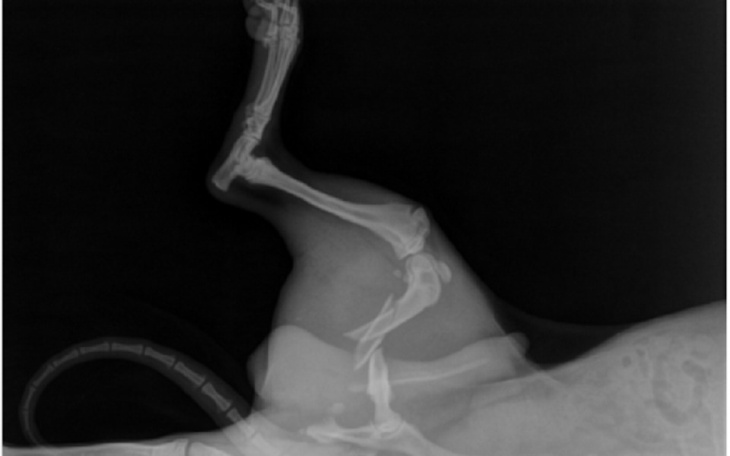

Odi to 7.miesieczny piesek z Zakopanego. Niedopilnowany, został potracony przez samochód i dziś bardzo cierpi. Koszty leczenia przerastają możliwości rodziny, nawet dla nas są bardzo wysokie. Sama operacja to koszt około 2000 zł, do tego wizyty kontrolne i zmiana opatrunków. Ewentualną nadwyżkę, przeznaczymy na zakup dobrej karmy, bo maluszek ma anemię i jest słabo odzywiony.